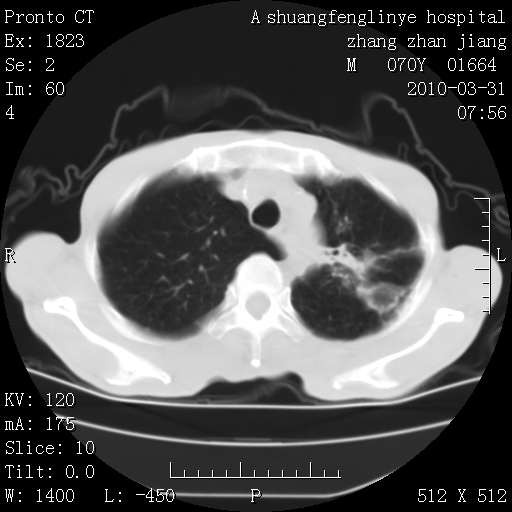

双上肺继发型tb并左上空洞形成,主动脉冠脉钙化。

支持:继发性肺结核伴空洞形成!建议纤支镜检查待出外周围型肺癌可能!

1)两肺上叶继发性肺结核并左肺上叶空洞形成。2)冠状动脉及主动脉钙化。